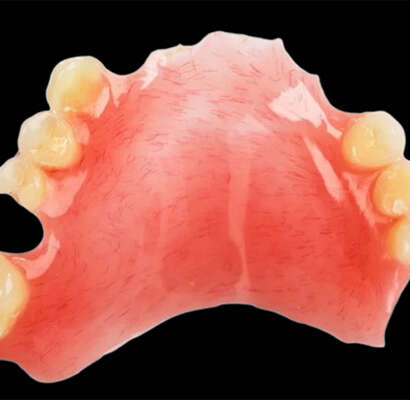

Partial acrylic dentures are detachable prosthetic appliances that are designed to replace one or more missing teeth in either the upper or lower jaw. Made of superior quality acrylic resin and artificial teeth, the dentures are designed to fit each patient‘s oral cavity shape—providing comfort, functionality, and a natural look.The design incorporates forged metal clasps that provide stable retention by anchoring to adjacent teeth.

Bestodental makes high-tech-fabricated precision partial acrylic dentures using CAD/CAM technology and high-tech fabrication. With their cost-effectiveness and practicality as a solution to fixed restorations, they are ideal for patients in need of cost-effective tooth replacement that doesn’t compromise esthetics. With the exception of patients with an acrylic allergy or advanced periodontal disease, our dentures are trusted by dental professionals worldwide for their versatility, durability, and exceptional clinical performance.